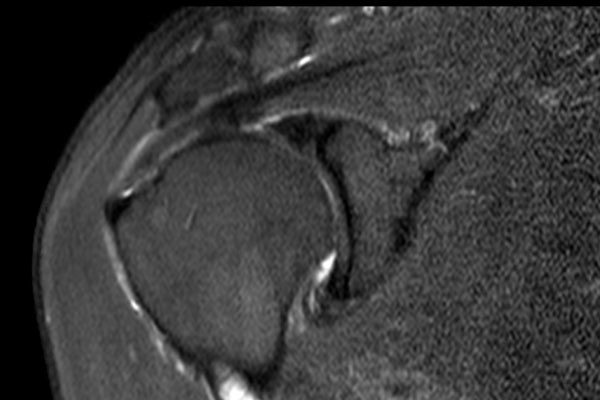

Nhấp vào hình ảnh để phóng to, sau đó cuộn qua các lát cắt.

Có hình ảnh rách toàn bộ chiều dày gân cơ trên gai kèm co rút và teo cơ.

Lưu ý các dải mỡ trong cơ tròn bé, cơ trên gai và cơ dưới gai.